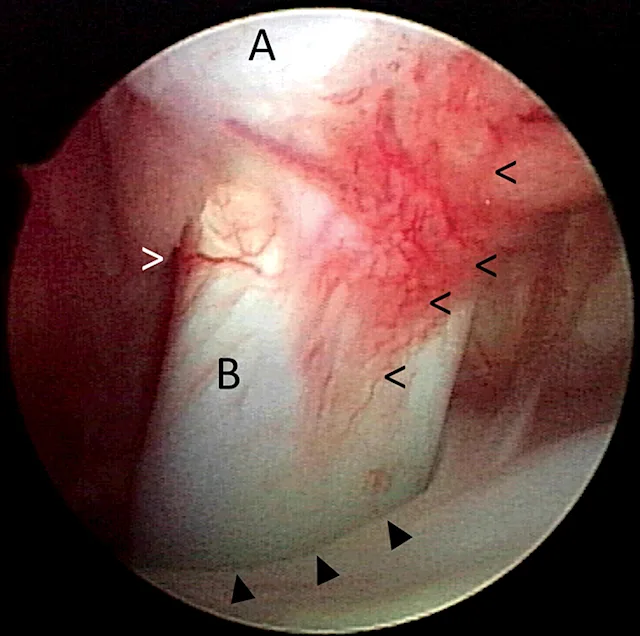

Biceps tenosynovitis is a common cause of forelimb lameness that most frequently affects medium- and large-breed dogs secondary to repetitive fatigue. It is characterized by inflammation of the biceps brachii tendon and the synovial sheath that envelops it in the shoulder joint (Figure 1).1,2 Clinical presentation often consists of a chronic progressive forelimb lameness that is worsened by exercise. The severity of lameness can vary from mild to nonweight-bearing, and atrophy of the supraspinatus and infraspinatus muscles is often present (Figure 2). Pain may be elicited during the biceps test, in which pressure is applied on the biceps tendon in the intertubercular groove when the shoulder is flexed and the elbow extended (Figure 3).1,2 Additional diagnostics (eg, ultrasonography, MRI, arthroscopy) are often needed to confirm diagnosis.1-3 Medical management (eg, rest, NSAIDs, physiotherapy) often results in resolution of mild lesions.1-3 Some dogs may require biceps tendon release or tenodesis to resolve pain and lameness.1-3

Arthroscopic image of the shoulder joint of a dog with biceps tenosynovitis. The biceps tendon (B) originates on the supraglenoid tuberosity of the scapula (A) and traverses distally through the bicipital groove of the humerus (closed arrowheads). Synovitis and increased vascularity of the tendon sheath are present (open arrowheads).